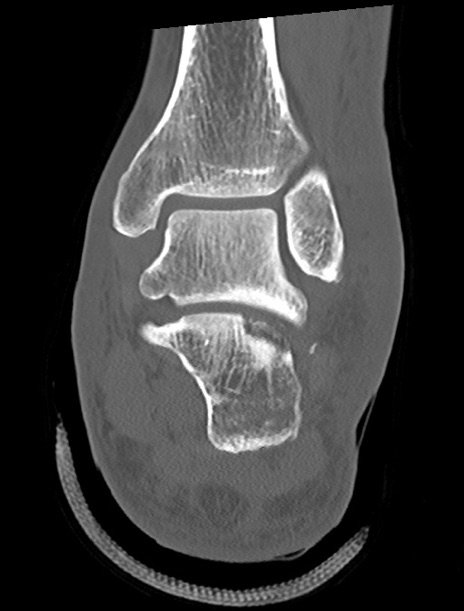

左足関節CT

矢状断像